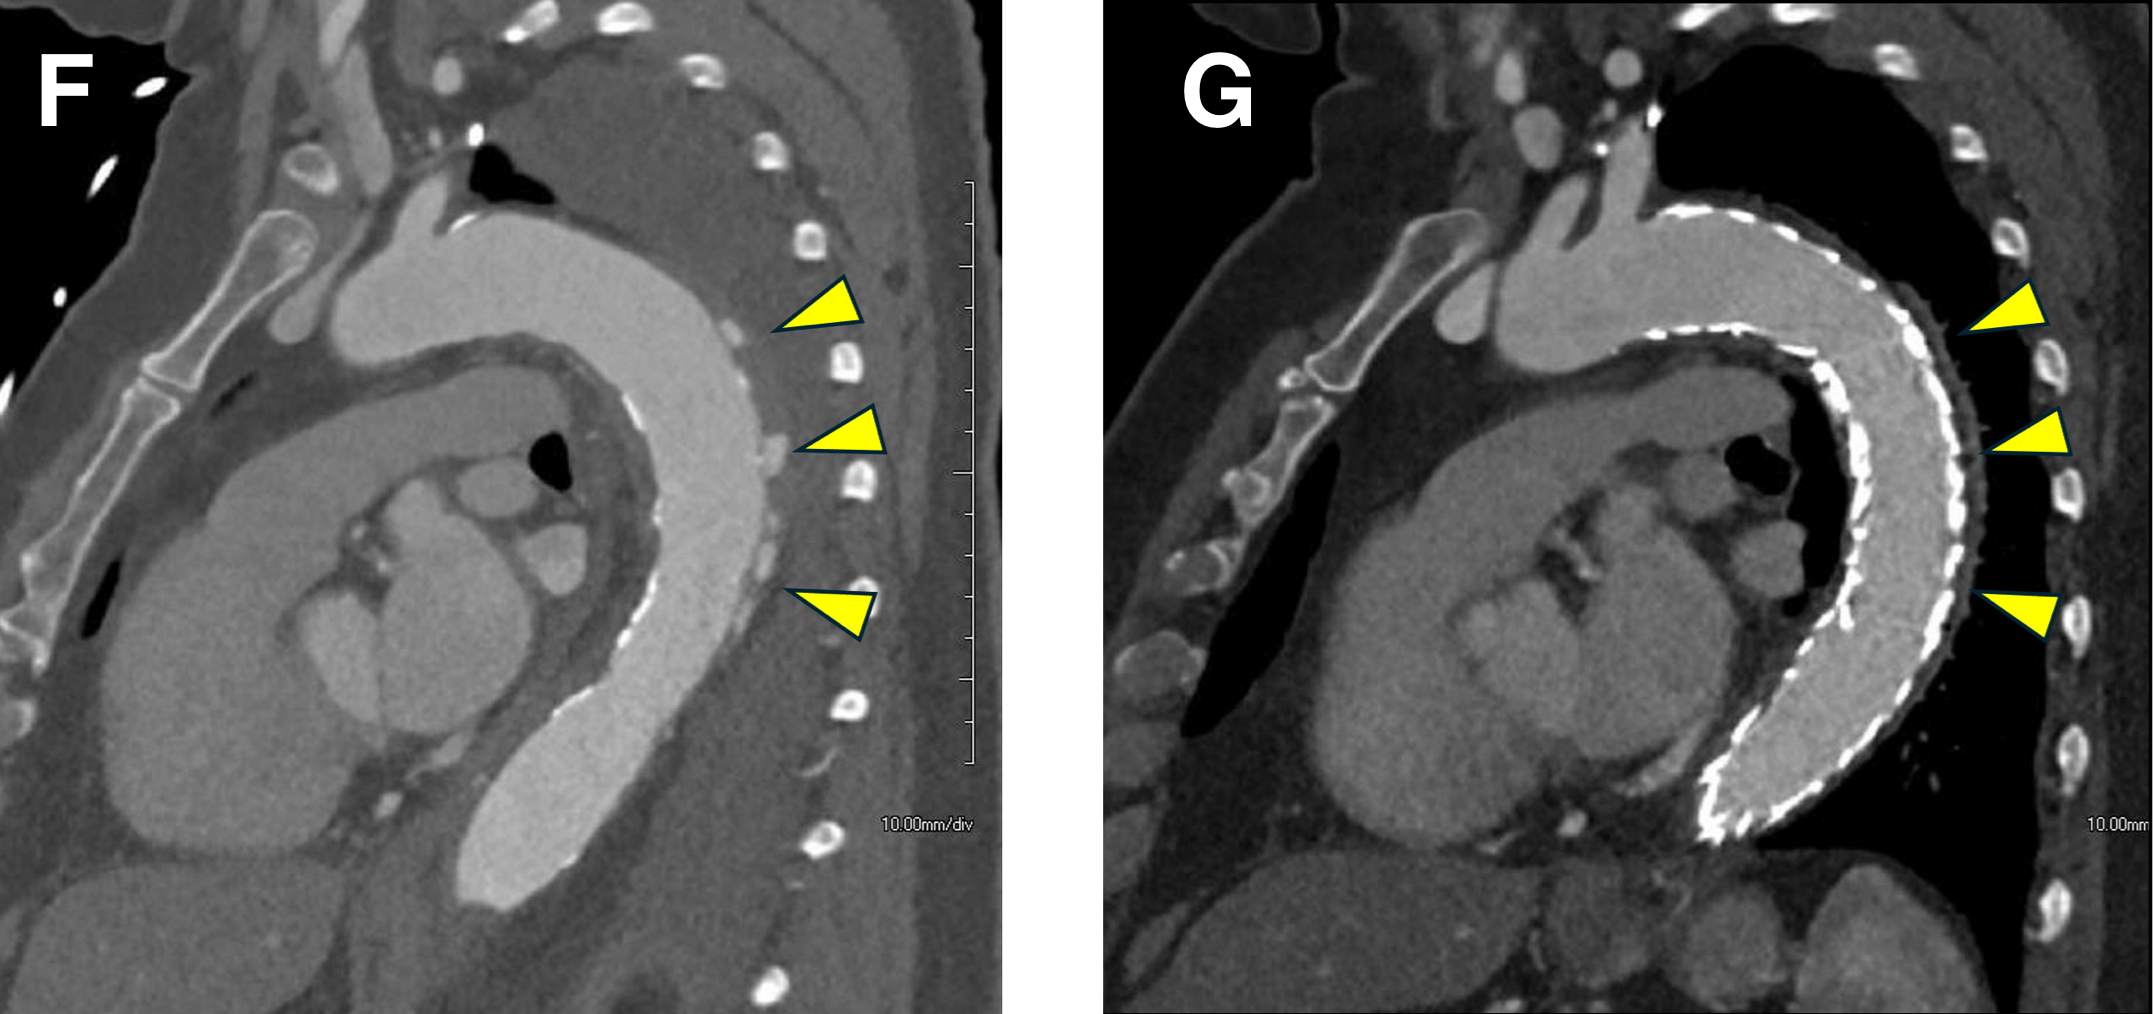

Figure E-F: Treatment of Intramural Hematoma (IMH)

Figure E. Sagittal MPR image before treatment shows ulcer-like lesions and adjacent intramural hematoma (arrowheads).

Figure F. Status post Thoracic Endovascular Aortic Repair (TEVAR). The ulcer-like lesions are no longer identified, and the IMH / aortic mural thickening has decreased (arrowheads).

Figure G-H: Treatment of Intramural Hematoma (IMH)

Figure G: Sagittal subvolume VR image before treatment shows ulcer-like lesions (arrowheads).

Figure H: Sagittal subvolume VR image after treatment. The patient is status post Thoracic Endovascular Aortic Repair (TEVAR). The ulcer-like lesions are no longer identified (arrowheads).

IMH can be categorized like aortic dissection using the Stanford classification: Type A IMH involves the ascending thoracic aorta, whereas type B dissection does not. Likewise, treatment is similar to aortic dissection: surgery / endovascular treatment for type A IMH, and medical management of type B IMH. When type B IMH becomes complicated (persistent pain, endo organ dysfunction, significant enlargement of aortic caliber), endovascular treatment (TEVAR) is often performed.